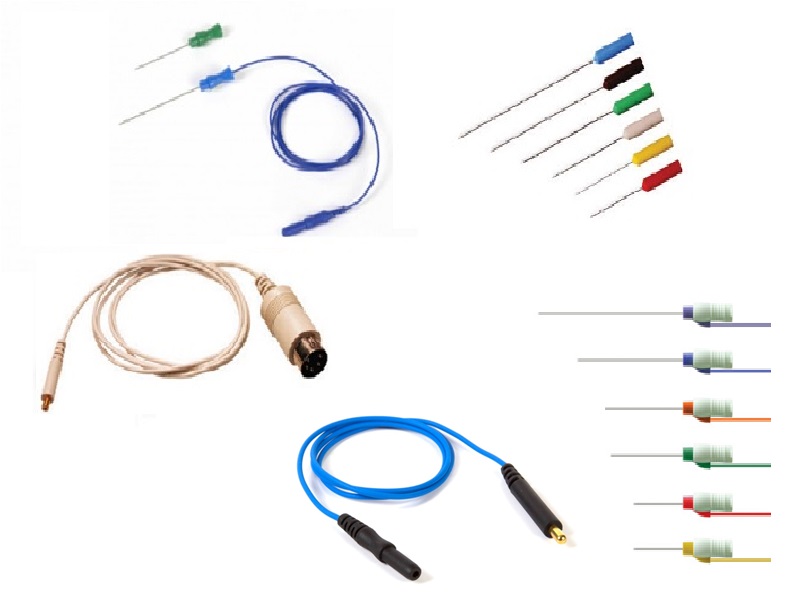

- Eletrodos de agulhas

- Eletrodos de Agulhas para EEG/PE/IOM